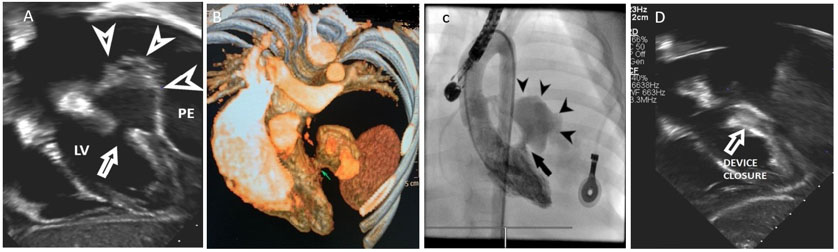

Her general condition did not improve and developed skin petechial and finger swellings. Her symptoms did not fit into criteria of specific systemic diseases. All laboratory investigations were unremarkable. Echocardiography showed pericardial effusion and LV posterior wall pseudoaneurysm. Cardiac tomography documented the findings (Figure 2).

After discussion with the team, it was decided to take her for percutaneous device closure of the aneurysmal orifice under guide of fluoroscopy and TEE using Amplatzer Muscular Occluder device size 12 mm through a retrograde approach (Figure 2). The procedure was uneventful.

In the following day, the echocardiography showed device in place closing the aneurysmal defect with no flow and mild pericardial effusion (Figure 2).

Figure 2: (A) The pericardial sac and LV posterior wall aneurysm with blood flow in-and-out between the LV cavity and the aneurysm lumen. The aneurysmal orifice is well seen (arrow head). (B) CT shows LV posterior wall aneurysm with blood flow in-and-out between the LV cavity and the aneurysm lumen. The aneurysmal orifice is well seen (arrow head). (C) LV angiogram shows huge aneurysm posterior to the LV wall (upper arrow), and the other lower arrow head pointing to the aneurysmal orifice showing the contrast leak from LV to the pseudoaneurysmal sac. (D) The aneurysm posterior to LV (upper arrow head) and Amplatzer devise covering the aneurysmal orifice.